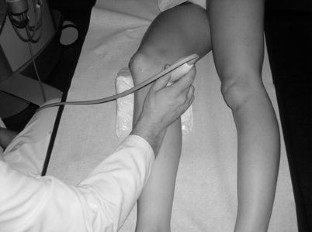

Abb. 2